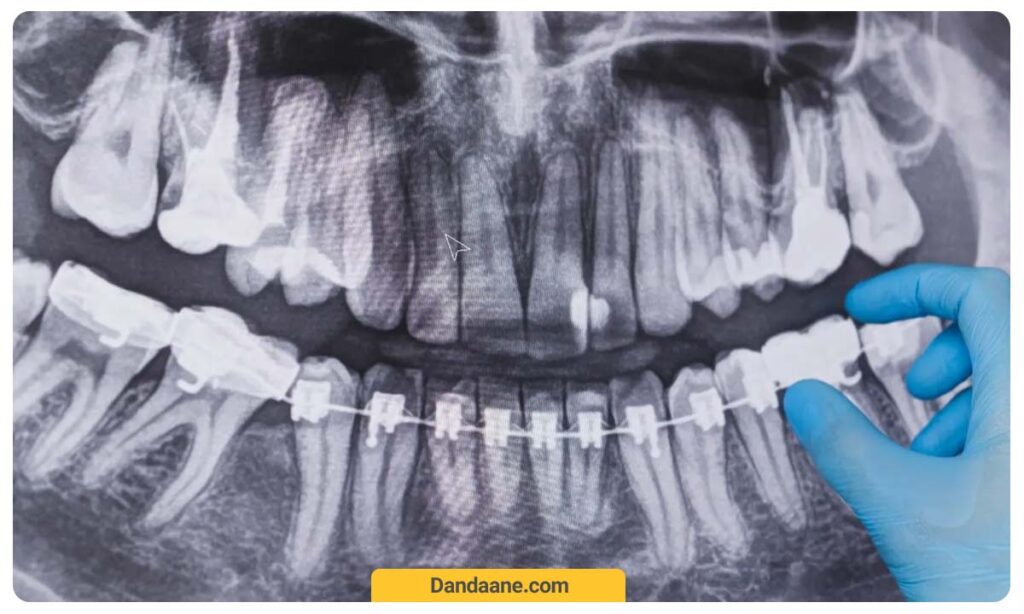

عکس پانورامیک (OPG)

این نوع عکس یک نمای کلی از تمام فک بالا و پایین، دندان ها و مفاصل فکی را ارائه می دهد.

کاربرد اصلی:

تشخیص کلی پوسیدگی ها، مشکلات فکی و دندان های نهفته.

آموزش خواندن عکس دندان

برای تشخیص پوسیدگی دندان در عکس opg، به بخش های تیره و روشن این عکس توجه کنید، نواحی تیره روی عکس opg به معنای پوسیدگی دندانی است. مسلما هر چه نواحی تیره روی عکس دندان بیشتر باشد، به معنای پوسیدگی بیشتر دندانی است.

نکته مهمی که باید به آن توجه داشته باشید این است که نواحی تیره (حتی کوچک) باید به سرعت تحت درمان قرار بگیرند تا قبل از اینکه به بافت نرم و زنده دندان (پالپ) برسد و منجر به عفونت دندان، تحریک اعصاب و حتی مرگ اعصاب دندان شود، از پیشرفت آن جلوگیری کنید.

نقاط تیره در عکس OPG دندان

نقاط تیره در عکس دندان نشان دهنده پوسیدگی و آسیب دیدگی دندان است. تیره بودن این نواحی در عکس دندان به دلیل کاهش تراکم بافت سخت دندان مانند مینای دندان در آنجا است. در واقع پوسیدگی دندانی باعث تحلیل بافت مینای دندان می شود و به همین دلیل اشعه های ایکس به راحتی از این ناحیه عبور می کنند و در تصویر نیز تیره رنگ دیده می شوند.

نقاط روشن در عکس OPG دندان

نقاط روشن روی عکس دندان، نشان دهنده بافت های سخت دندان مانند ریشه و عاج دندان است. به دلیل اینکه این بافت ها سخت تر و با تراکم بالاتری هستند، از عبور اشعه ایکس از داخل آنها جلوگیری می کنند و در نتیجه در تصویر به شکل نقاط روشن نشان داده می شوند. در واقع نقاط روشن در عکس دندان به معنای سالم بودن دندان است.